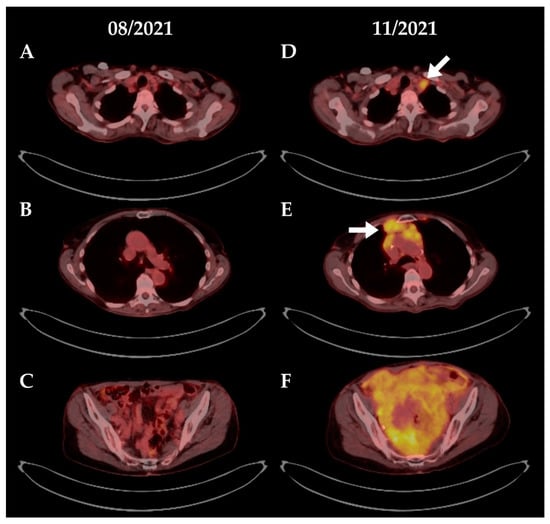

4.1. Patient #1

4.2. Patient #2